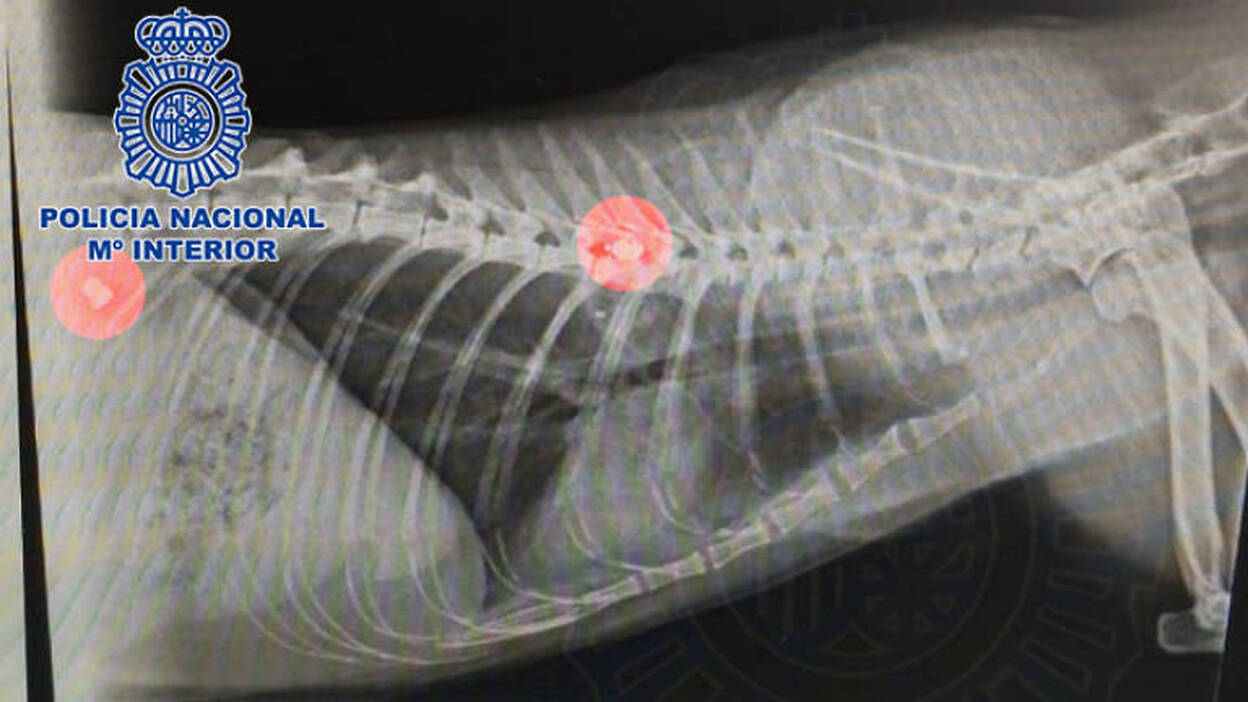

Mató a la gata de sus vecinos, disparándole con una escopeta de aire comprimido. El animal falleció a consecuencia de los impactos de dos proyectiles, uno de los cuales se alojó junto a su columna vertebral. El arrestado reconoció ante los agentes haber sido en autor de los disparos.

Los agentes se entrevistaron con testigos y vecinos de un complejo residencial de Maspalomas, además de recabar la información de la clínica veterinaria donde fue asistida la gata tras su muerte. Se aportó una radiografía del animal donde se observaban los proyectiles alojados en el interior de su cuerpo, uno de ellos junto a la columna, que le produjeron la muerte.